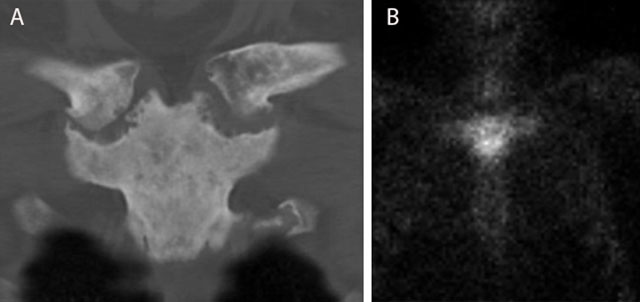

The combination of synovitis, acne, pustulosis, hyperostosis and osteitis is designated as SAPHO and is seen as the adult counterpart of CRMO. It represents an inflammatory disorder of unknown etiology in which osteitis is a key symptom. The axial skeleton is preferentially affected with predominant involvement of the sternoclavicular joints (bilateral sternoclavicular joint edema) (Figure 14) and the spine. Sacro-iliac joints are not commonly involved.

Figure 14

Typical bullhead sign in SAPHO of the sternoclavicular joint. CT (coronal reformatted image) (a) shows sclerosis of the manubrium sterni and medial clavicles and erosions of the sternoclavicular joints. Note a typical bullhead sign on scintigraphy (b).

In SAPHO, the affected joints show sclerosis and erosions of the joint facets which are all signs of arthritis. Hyperostosis and enthesopathy are visualized [20].

CT is able to detect and assess the extent of these bony changes with precision [19].